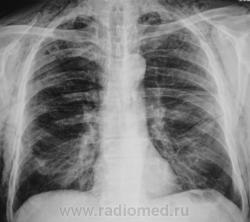

Шикарная эмфизема мягких тканей, перелом 8 -го ребра справа по задней подмышечной линии (как минимум)....

Этого пациента, сегодня дали на контроль. Первичная рентгенограмма от 8.05., там плюсом, имело место коллабирование правого легкого на 2/3.

Да весьма показательный, яркий случай!

А справа в нижних отделах кальцинат?